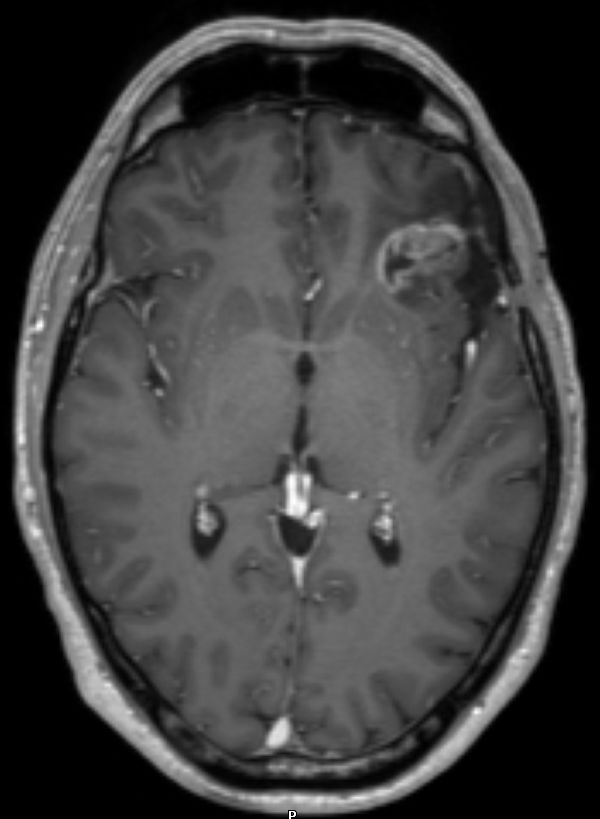

| Kasuistik 1 | 33jährige Frau mit einem links-frontalen Gliom Grad 2.